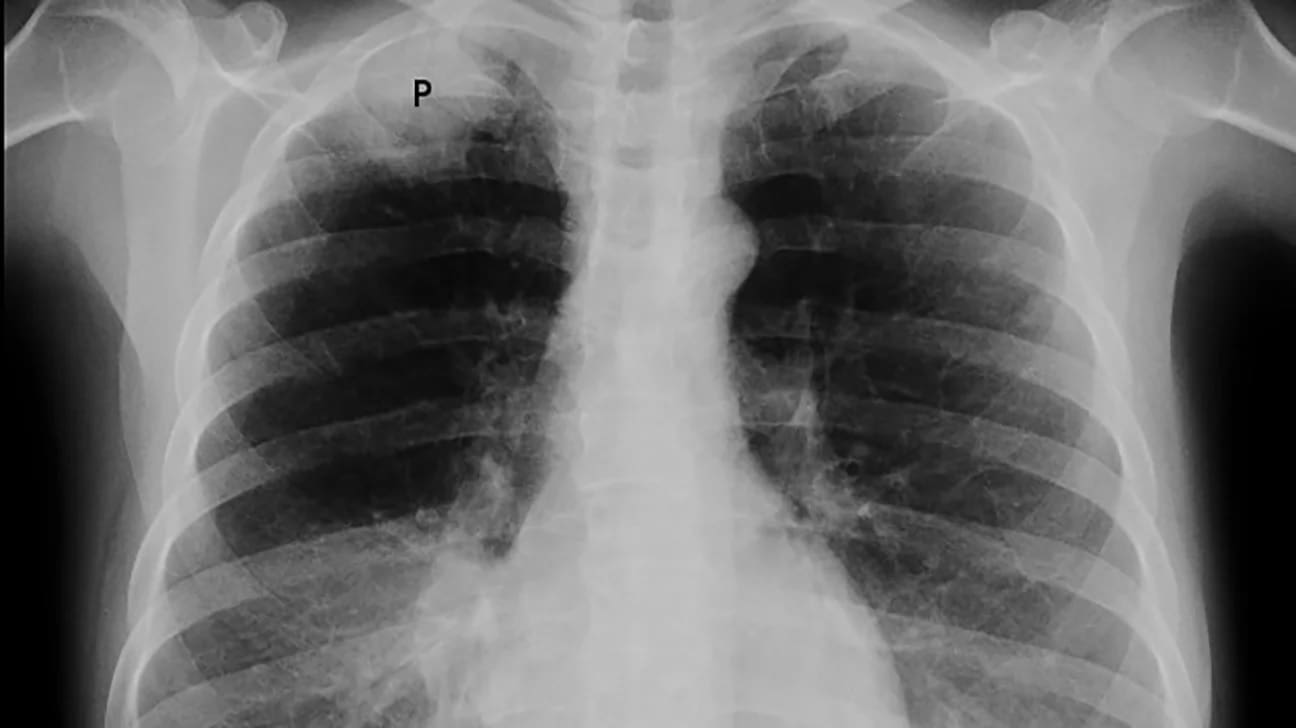

- Rx tórax: masa paravertebral izquierda a nivel de T8-10.

- TAC de tórax: Masa de mediastino posterior al nivel de T9 con invasión de cuerpo vertebral. (Figura No 1)

Figura No. 1 Tac: masa gavabertebral izquierda que aumenta la amplitud del fovamen de conjugación del cuerpo vertebral adyacente ,erosión osea del cuerpo vertebral y del pediculo.feocromocitoma Extr-adrenal.